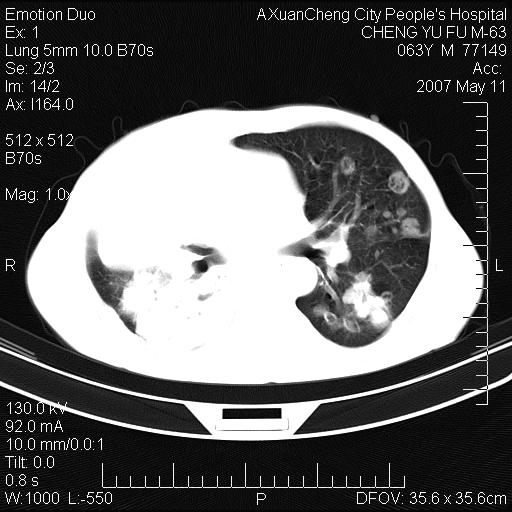

以下是引用小初学者在2007-5-11 19:32:00的发言:[br]1、首先考虑干酪性肺炎支气管播散[br]2、支气管肺泡癌待排

以下是引用zhangzhongshou在2007-5-11 19:30:00的发言:[br]细支气管肺泡癌可能性大。